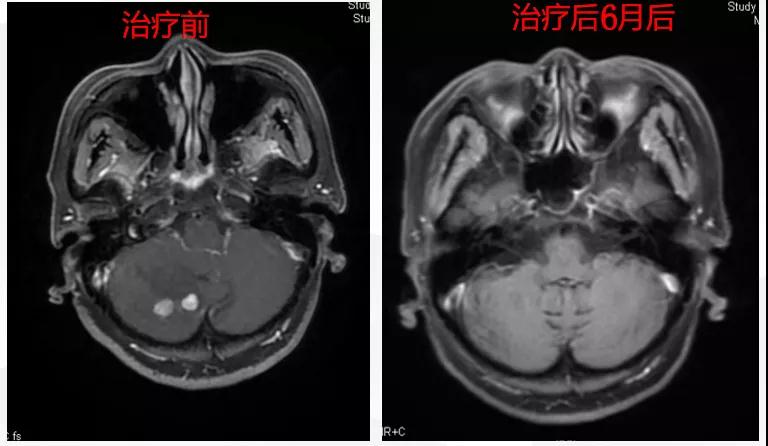

曲妥珠单抗辅助治疗结束6个月后,患者出现左侧胸部疼痛,ECT检查提示:左侧第4、5肋骨及T2胸椎转移;MR提示:T2椎体转移,肝S6段异常强化灶,考虑转移瘤可能性大;脑转移(图1)。

图1